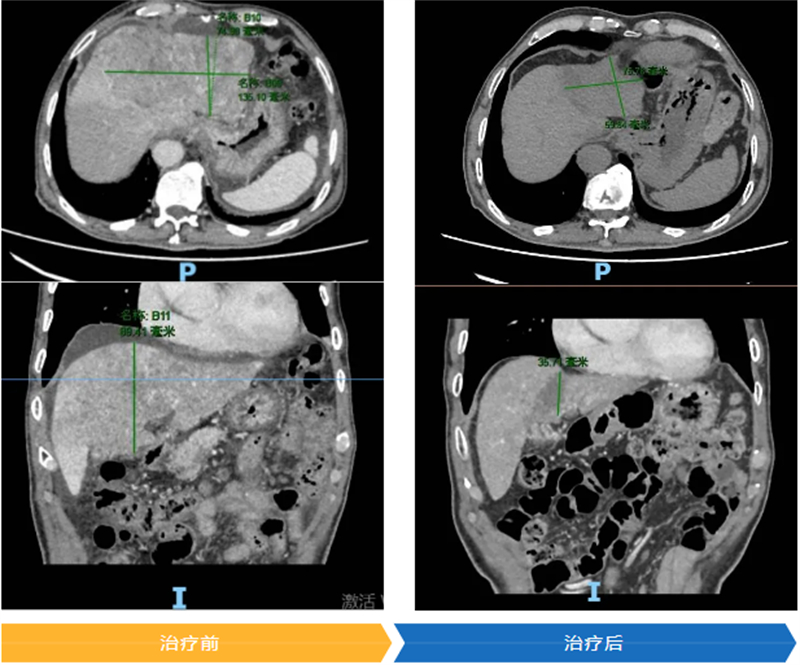

入院后,肝癌多学科联合诊疗专家团队迅速对罗大叔的病情进行联合会诊。其肝癌病灶最大直径已达12.2cm,还侵犯了门静脉右后支、肝右静脉,左肝体积不足,根据原发性肝癌诊疗指南,已不适合直接手术。不过,专家团队发现罗大叔左边肝脏未受癌细胞侵袭,于是为他量身定制了“靶向+免疫+介入”三联转化治疗方案。

经过2个周期的治疗,罗大叔的肿瘤标志物降低,几乎接近正常水平;功能性影像检查肝肿瘤缩小,侵犯静脉的瘤栓消退,肿瘤活性降低,左肝代偿性增生,成功转化为可手术状态。2025年3月,医生顺利切除了罗大叔的肿瘤。术后病理回报显示,肝癌病灶中未见存活肿瘤细胞。在快速康复外科理念的指导下,罗大叔术后1周便顺利出院。出院时,医生还特别叮嘱他,要遵照医院的肝癌全程管理方案,继续进行后续的综合治疗,以降低肿瘤复发的风险。